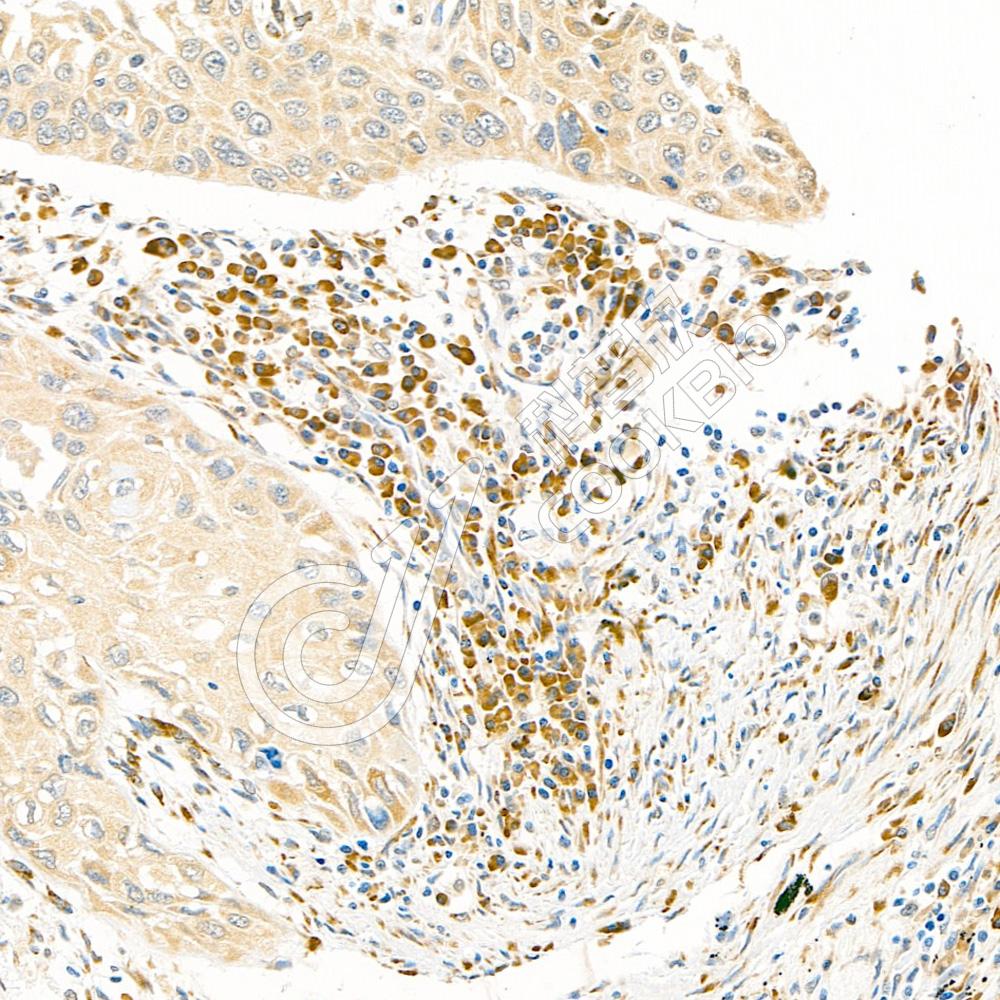

IHC检测Ki67蛋白(货号 K5450069).

样品: 人食管癌, 4%多聚甲醛 (货号KSG1101) 固定12-24小时.

抗原修复: 柠檬酸抗原修复液(干粉, pH 6.0) (KSG1201), 高压锅均匀喷气计时2分钟.

—抗: 1: 2000稀释, 4℃ 孵育过夜.

二抗: S-vision免疫组化多聚二抗(山羊抗小鼠), 即用型(货号KB3903), 室温孵育20分钟.